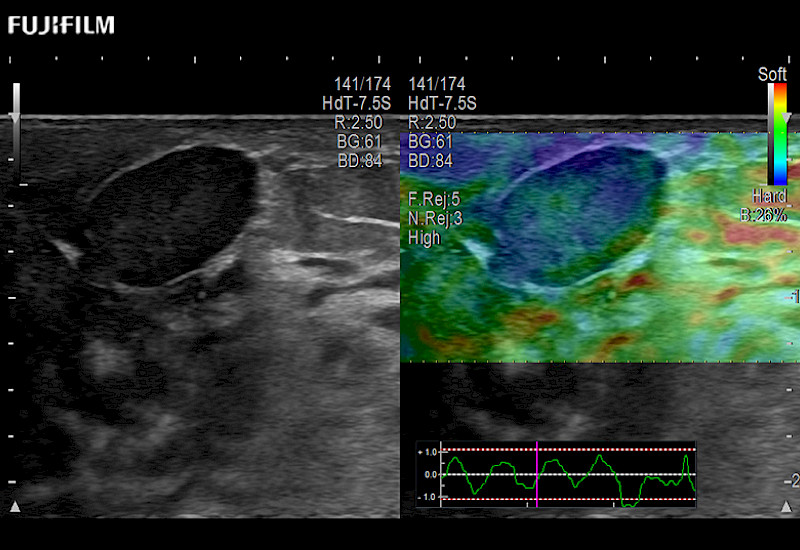

For precise surgical oncology ultrasound imaging, Fujifilm Healthcare offers premium level solutions that include:

Extraordinary high-resolution digital imaging

Multi-Parametric imaging modalities

Our dedication to Surgical Oncology allows us to offer superior image quality, outstanding system reliability and intuitive use of cutting edge technology.

ARIETTA 750 for Surgical Oncology

The ARIETTA 750 incorporates all of the proven technologies and functions that medical professionals have come to expect from Fujifilm Healthcare.

ARIETTA 750 is the definitive diagnostic ultrasound solution for any clinical setting - Private Office, Imaging Center, or Hospital. The ARIETTA platform provides the ultimate in clinical performance with its state-of-the-art features and large user-friendly display.

ARIETTA 650 DI for Surgical Oncology

The ARIETTA 650 DI combines trusted Fujifilm Healthcare technologies and features tailored for surgical oncology.

Designed to meet the demands of surgeons, the ARIETTA 650 DI offers precise guidance. Its advanced capabilities and large, intuitive display offer accurate and efficient care in operating rooms and specialized surgical settings.